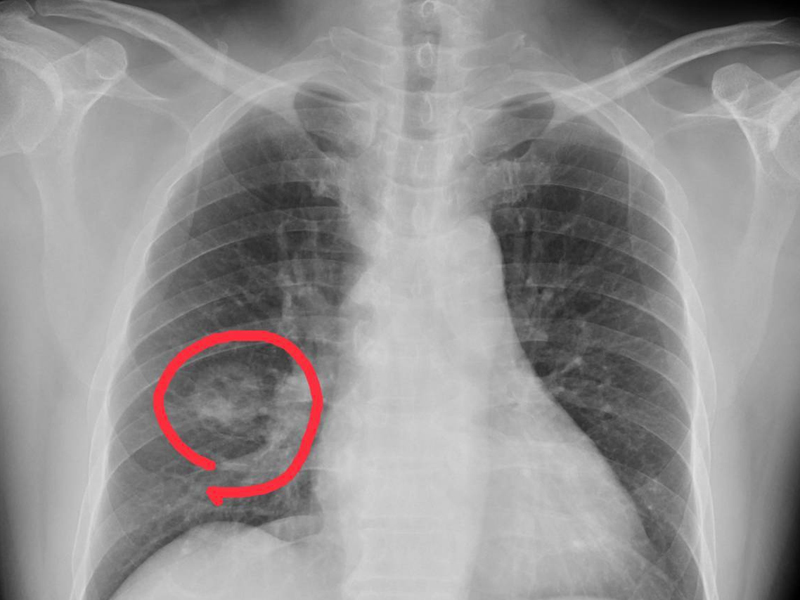

近日,中國江蘇省杭州市一名 50 歲的李姓婦女因雙腿莫名發癢兩個月而求醫,最終確診為原發性肝癌。起初,她以為是皮膚過敏,但服用抗過敏藥物後症狀並未改善,隨後連上半身也開始出現類似情況。最終,在衛生服務中心醫師的建議下進行腹部彩超檢查,發現肝臟異常,轉診至浙大二院進一步檢查後確診為肝癌。幸運的是,由於發現得相對及時,經過手術切除腫瘤,李女士正在逐步康復中。 身體發癢與肝癌的關聯 全科副主任醫師指出,肝臟是一個「悶葫蘆」器官,內部沒有痛覺神經,因此即便肝細胞損傷嚴重,患者也可能不會感到明顯不適。這使得肝癌在早期特別難以察覺,許多患者一發現病情即已進入晚期。李女士所經歷的皮膚瘙癢便是肝癌發出的一個警示信號,這種頑固性瘙癢是由於肝臟損傷激活了皮膚中的神經纖維,通過信號傳導至腦感覺皮層所致。 需警惕的四種皮膚異常 專家提醒,若皮膚出現以下四種異常情況,應當警惕可能是肝臟病變的徵兆: 皮膚瘙癢:肝臟損傷可能激活皮膚中的神經纖維,導致頑固性瘙癢。 皮膚發黃:肝功能受損會使體內膽紅素積聚,造成皮膚和眼白呈現蠟黃色。 蜘蛛痣:這是皮膚表面出現的小血管瘤,按壓時消失,放開後再次出現,通常與雌激素濃度升高有關。 出血:肝臟合成凝血因子的能力下降可引起牙齦出血、皮膚出血點或消化道出血等現象。 結語:健康不容忽視,定期檢查保平安 專家強調,對於這些看似普通的症狀,我們絕不能掉以輕心。一旦發現上述異常情況,應及時就醫進行詳細檢查,以便早發現、早治療,提高治愈率和生存質量。同時,保持良好的生活習慣和定期的健康檢查也是預防疾病的重要手段。 |